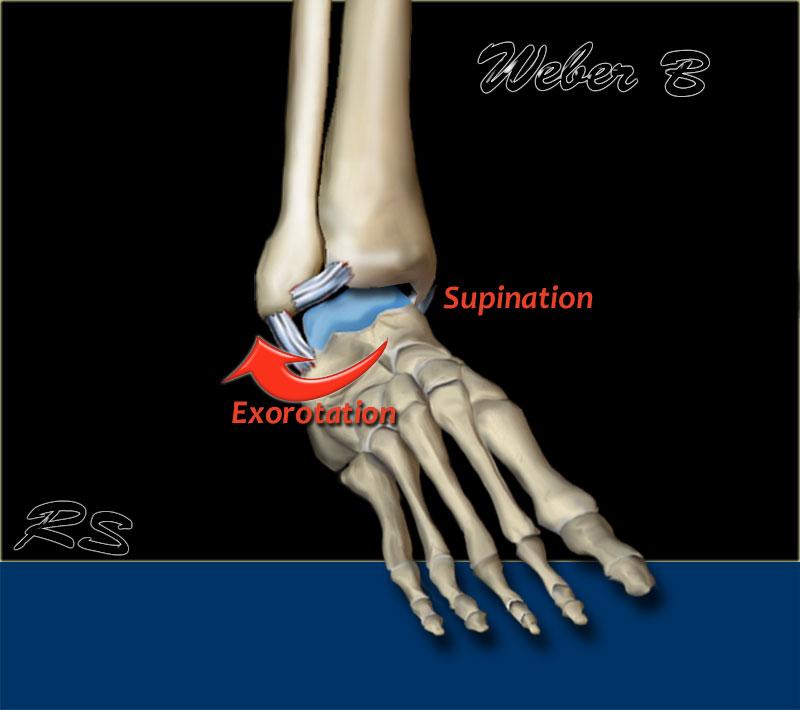

Weber B

Đây là gãy xương ngang khớp chày mác, thường kèm theo đứt một phần – và ít gặp hơn là đứt hoàn toàn – khớp chày mác.

Theo Lauge-Hansen, đây là kết quả của lực xoay ngoài tác động lên bàn chân ở tư thế sấp.

- Giai đoạn 1 – Đứt khớp chày mác trước

- Giai đoạn 2 – Gãy chéo xương mác (đây là gãy Weber B thực sự)

- Giai đoạn 3 – Đứt khớp chày mác sau

hoặc – gãy mắt cá sau - Giai đoạn 4 – Gãy giật mắt cá trong

hoặc – đứt các bó dây chằng bên trong

Weber B in detail

Weber B là loại gãy xương mắt cá chân phổ biến nhất, chiếm khoảng 60%.

Theo Lauge-Hansen, gãy xương này là kết quả của lực xoay ngoài tác động lên bàn chân ở tư thế sấp.

Theo Lauge Hansen, tổn thương đầu tiên xảy ra ở phía ngoài, nơi đang chịu lực căng tối đa.

Ở giai đoạn 2, xương sên tiếp tục xoay ngoài và do bàn chân đang ở tư thế sấp, mắt cá ngoài bị giữ chặt tại chỗ bởi các dây chằng bên ngoài.

Mắt cá ngoài không thể di chuyển ra ngoài mà không bị gãy.

Kết quả là sự xoay tiếp tục của xương sên sẽ gây gãy xương mác theo kiểu chéo hoặc xoắn ốc do mắt cá ngoài bị đẩy bật ra từ phía trước trong ra phía sau ngoài.